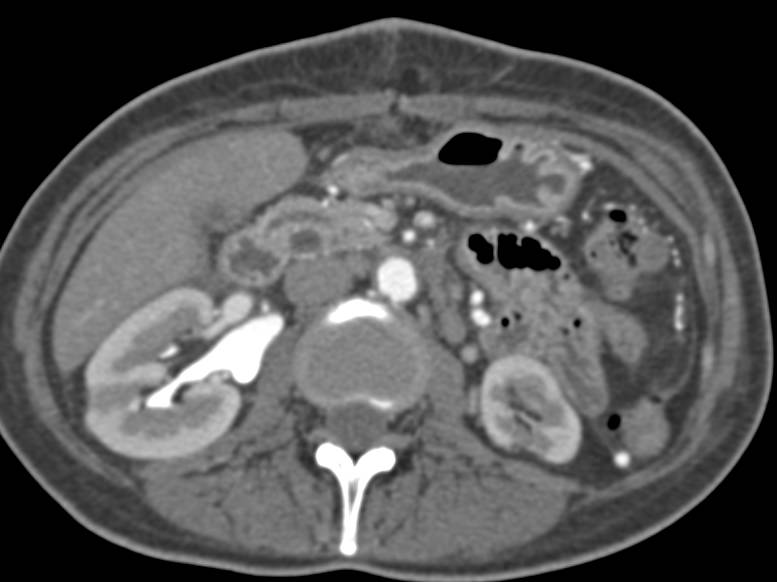

Nodes Near Head of Pancreas